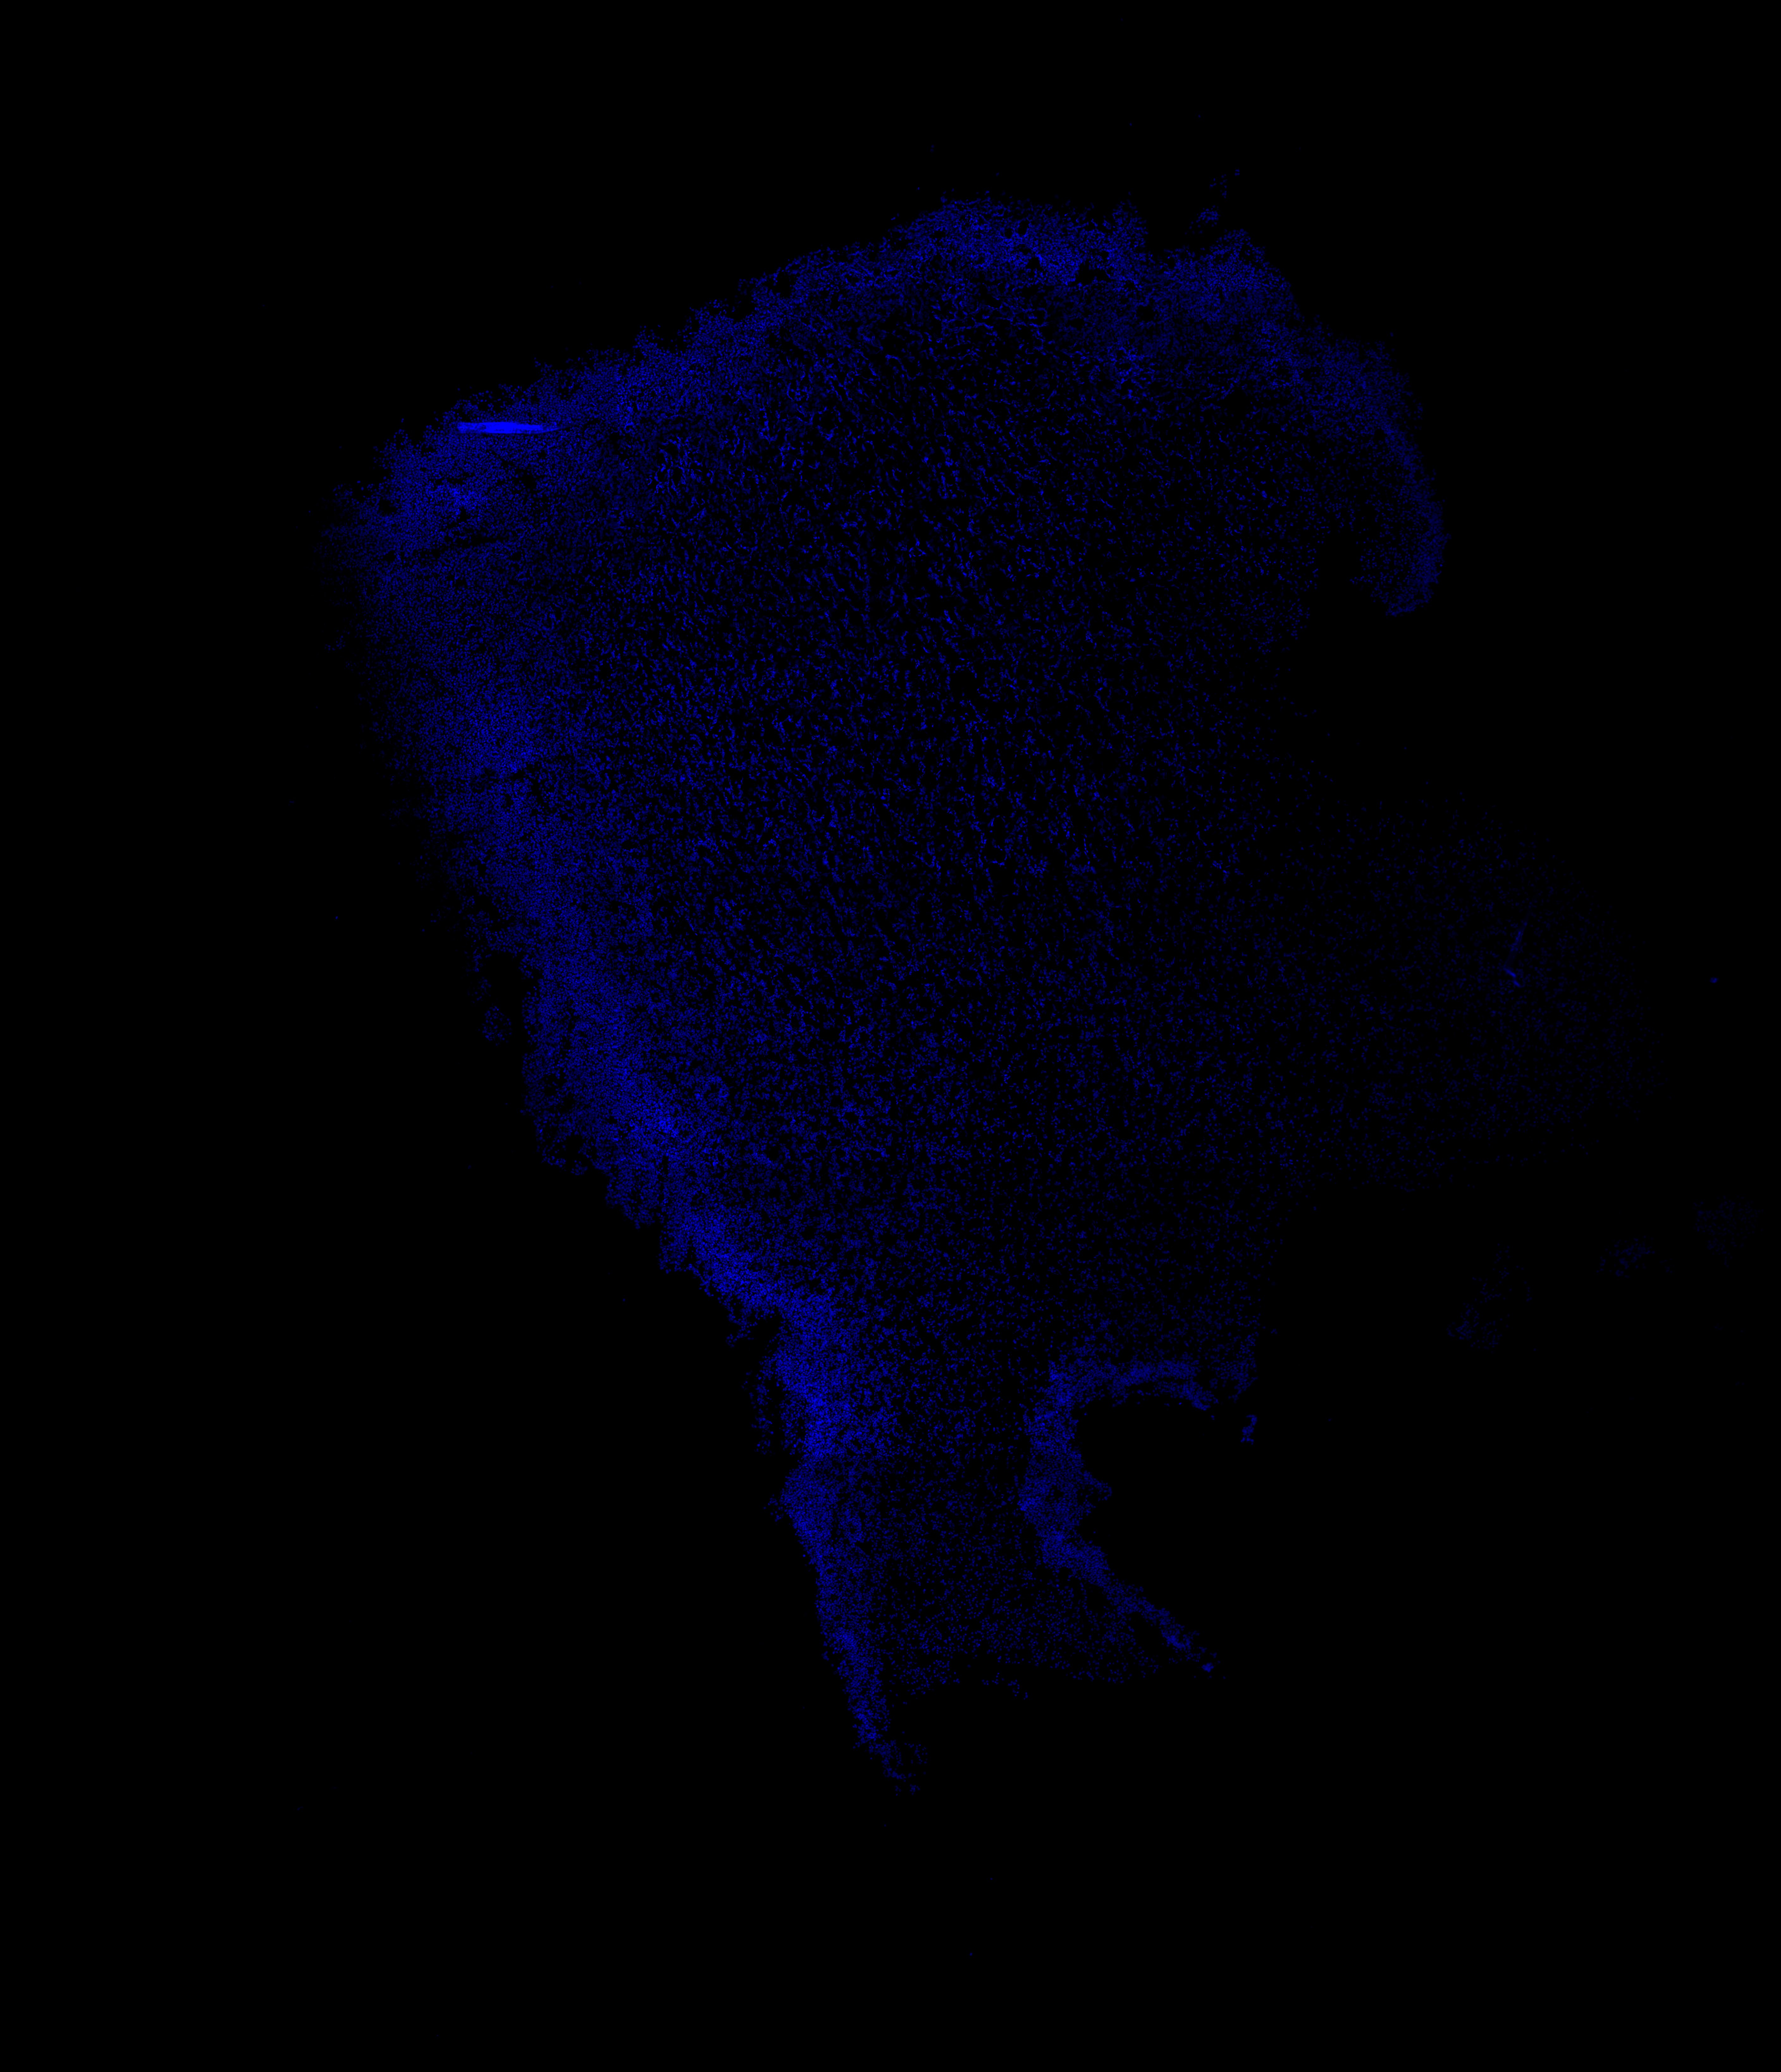

An anatomical analysis of the developing human midbrain from 6 post-conceptional weeks (PCW) to 22 PCW reveals increased tissue complexity, characterized by the emergence of dopaminergic nuclei, as highlighted by immunofluorescence analysis for tyrosine hydroxylase (TH).